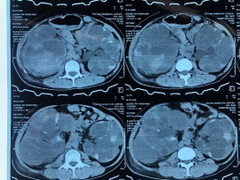

Khám cho bệnh nhân có những dấu hiệu trên, ngoài quy trình khám, bác sĩ có thể chỉ định các xét nghiệm để tầm soát bệnh thận như xét nghiệm máu, xét nghiệm nước tiểu, chẩn đoán hình ảnh...